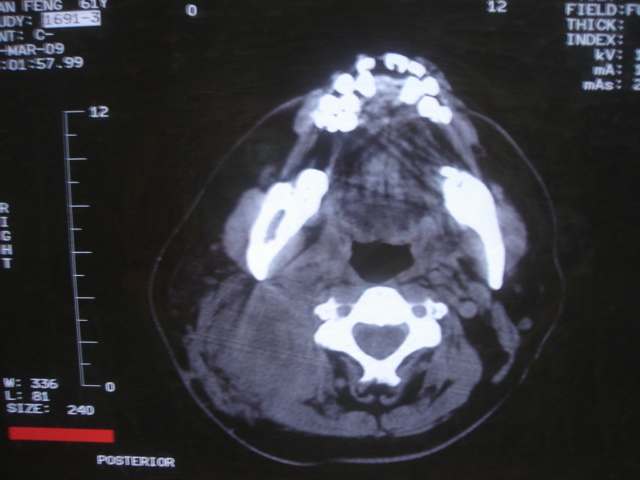

患者 男 61  甲状腺ca术后7年 颈部淋巴结转移

颈部多个淋巴结增大,结合甲状腺ca术后7年病史考虑转移。

右侧颈部淋巴结转移,右声带乳头突起,乳头状瘤可能性大。

1)右侧颈部淋巴结转移瘤。2)右侧声带新生物,性质待定;建议喉镜检查(活检)。

结合病史符合甲状腺ca术后颈部淋巴结转移